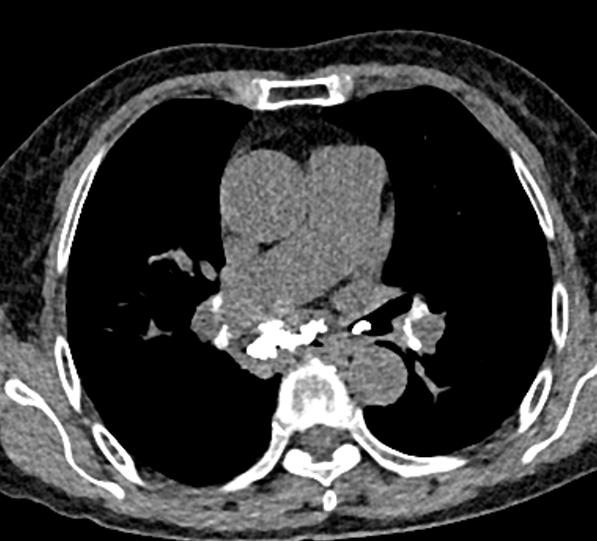

图1~图7 胸部CT示双肺多发钙化

问题在哪儿?

肺部钙化灶脱落,掉进左主支气管(图8),因为钙化病灶是坚硬的、锐利的,就像一个石头在不断地刺激支气管粘膜,导致患者咳嗽。

图8 胸部CT